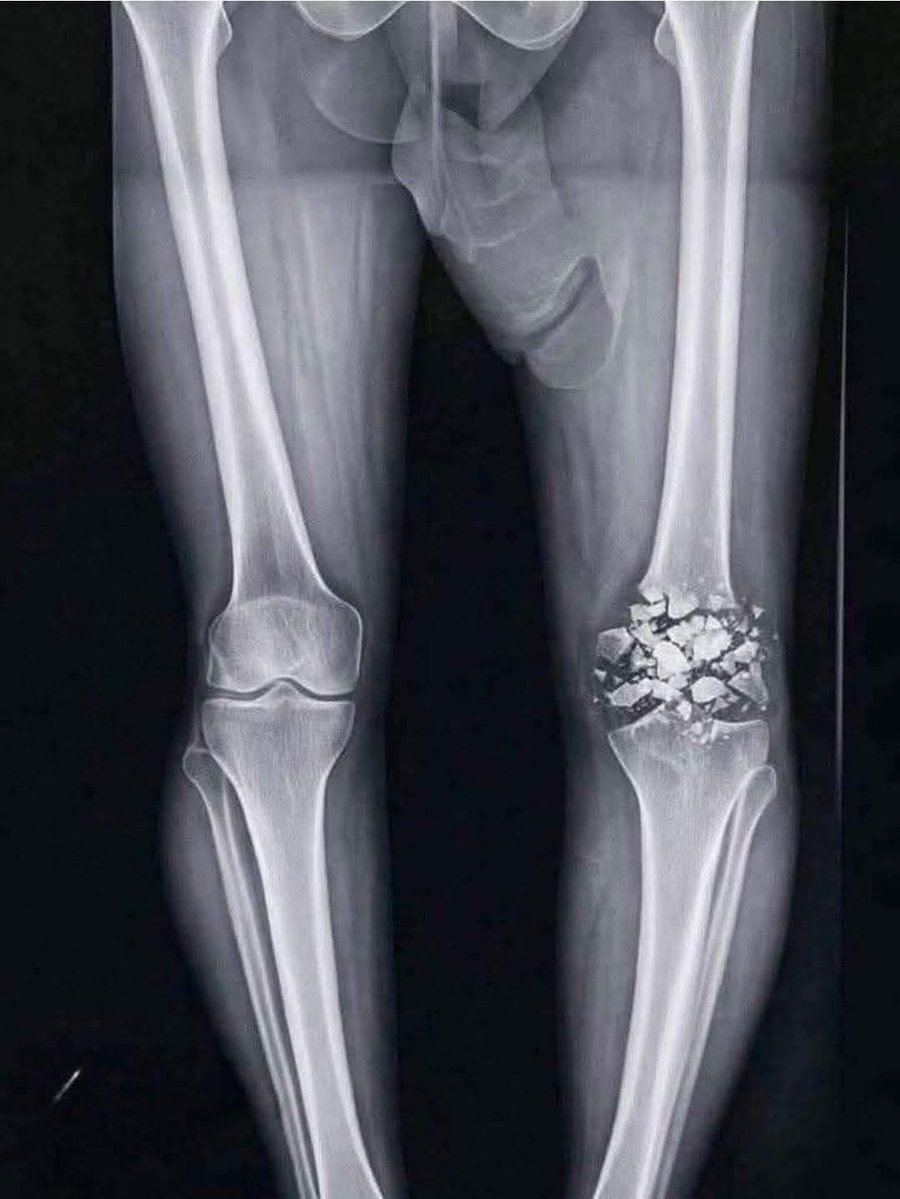

Wearing gloves at the gym is insanely gay Your hands should be looking like this after spamming hundreds of pullups every week